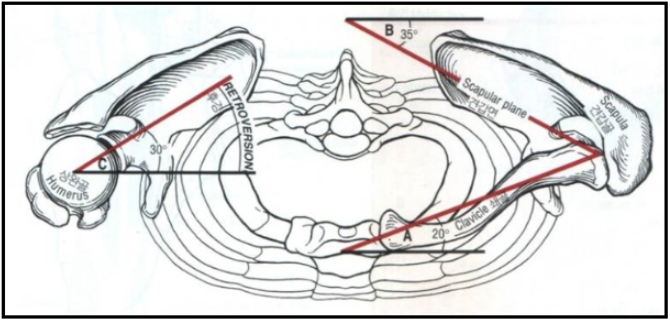

견갑골의 각도는 몸의 중심선(Coronal plane=frontal plane)으로부터 30 ~ 35도 기울어져 있고, 늑골에 거의 바짝 붙어있는것이 정상입니다.

일반적으로 팔을 벌리는(팔벌려 뛰기 동작) 외전과 다르게 견갑골 관절면(Scapular plane)을 따라서 팔을 들어올리는 것을 스캡션(Scaption) 이라고 하는데요.

스캡션(Scaption)시에는 해부적구조상 극상근의 결의 방향과 힘의 방향이 그대로 일치합니다. 따라서 초음파로 동적 검사(Dynamic test) 시 극상근의 파열을 더 잘보려고 할 때 스캡션(Scaption)을 하라고 하면서 저항을 주면서(Full can test와 동일) 극상근의 파열부가 벌어지는것을 초음파로 확인해줄 때 사용합니다.